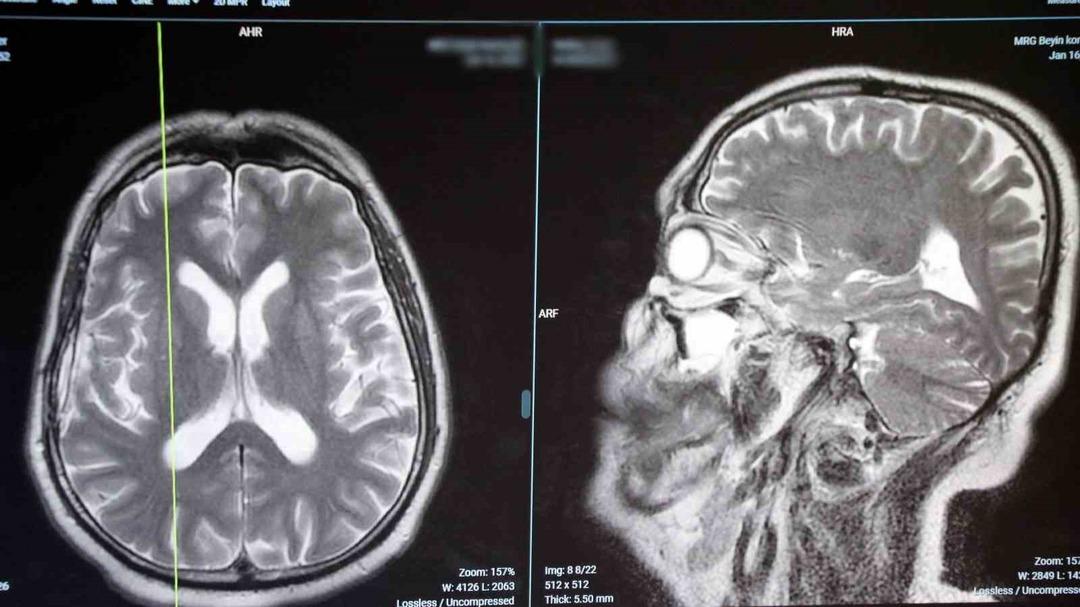

Koku halüsinasyonu nedir? “Beyin tümörü, parkinson ve epilepsi gibi ciddi hastalıkların habercisi olabilir”…

“Koku bozuklukları beyin kanseri, epilepsi ve parkinson gibi hastalıkların bir belirtisi olabilir”